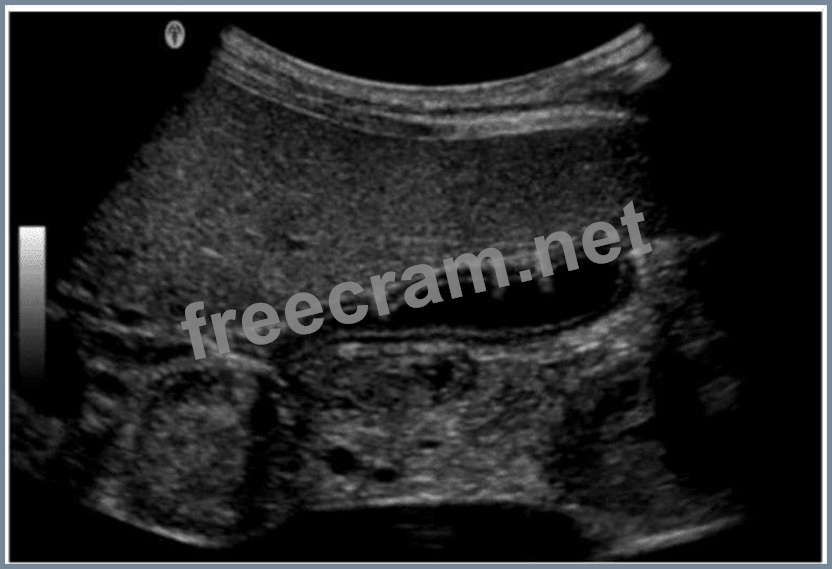

Which condition is most consistent with the findings in the image below?

Question 27: Which condition is most consistent with the findings in the ...